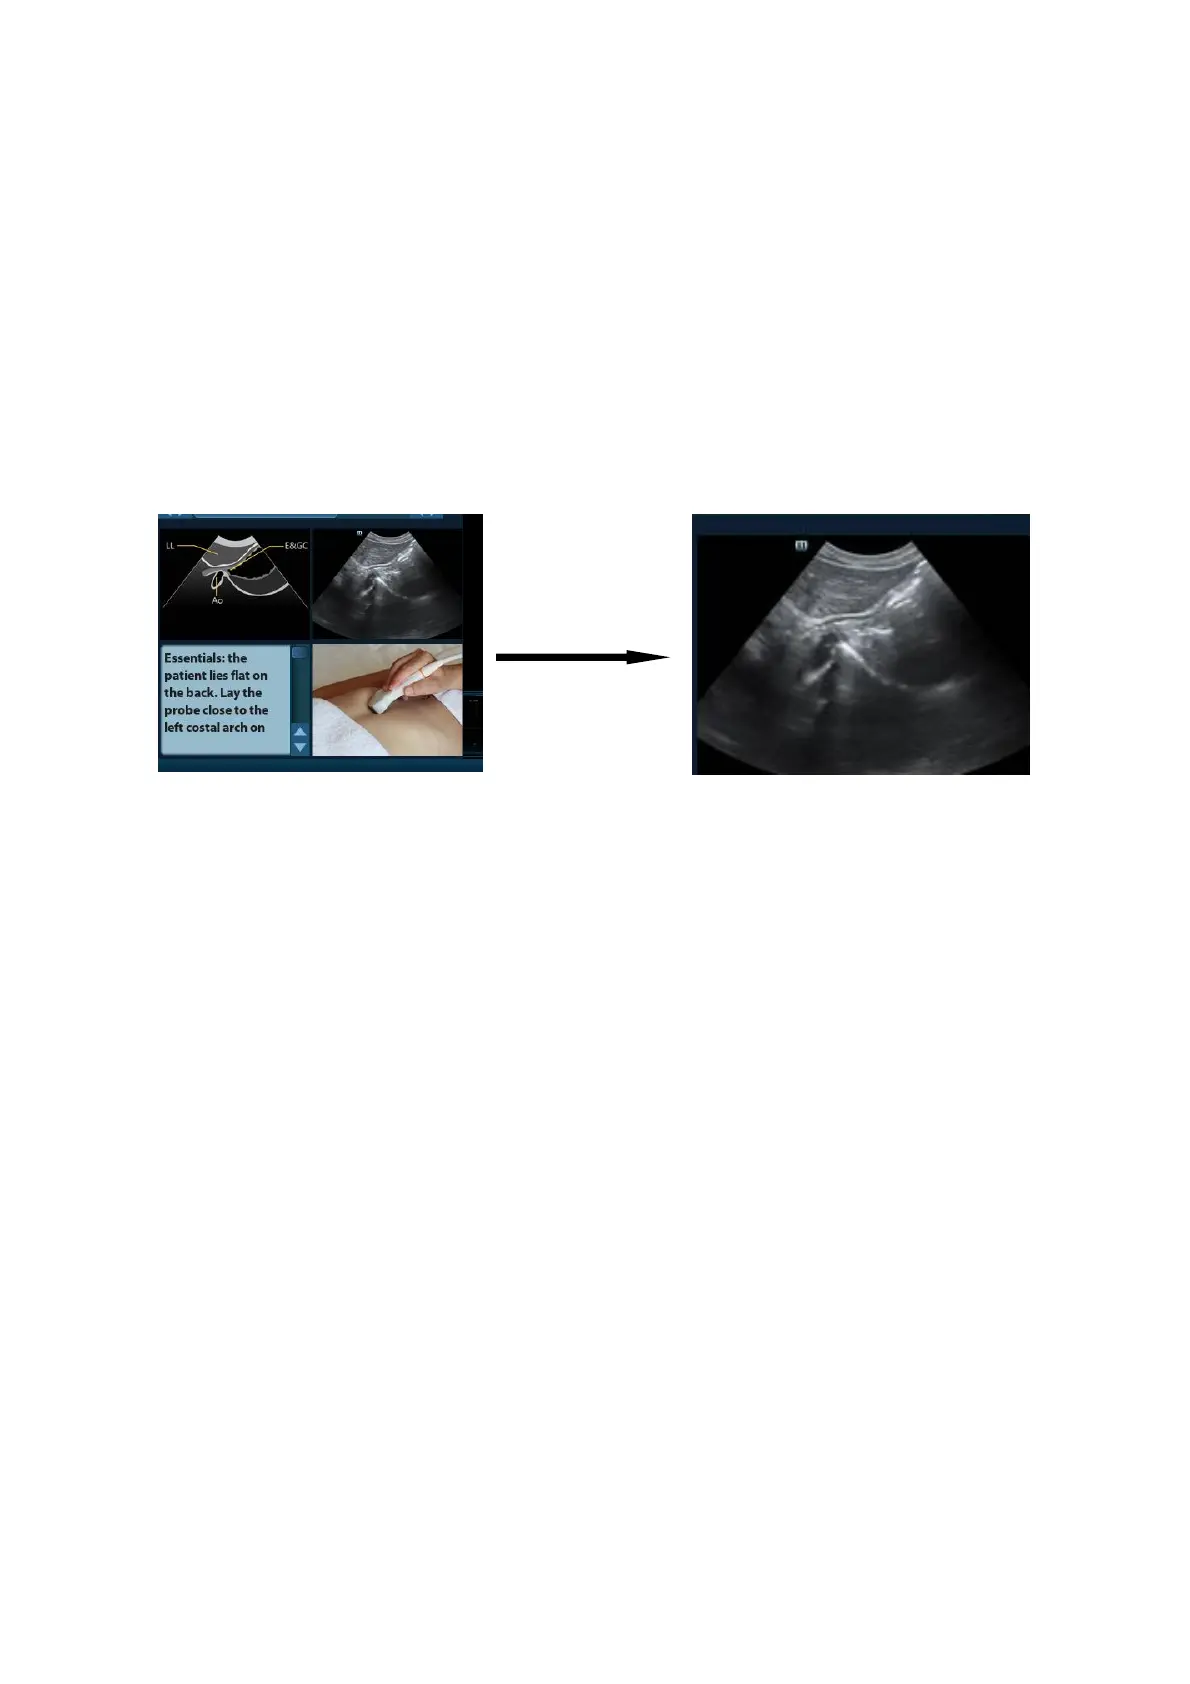

iScanHelper B-3

Scanning picture

Ordinary scanning tips can be observed here, including posture, probe mark, probe

swing/sweep techniques.

B.4.3 Single/quad-window Display

You can zoom in the anatomic graphic, ultrasonic image as well as scanning picture to view

those information more conveniently.

Press <Cursor> to obtain the cursor. Move the cursor on the anatomic graphic, the ultrasonic

image or scanning tips. Double-click <Set> to go to the single window of each of them.